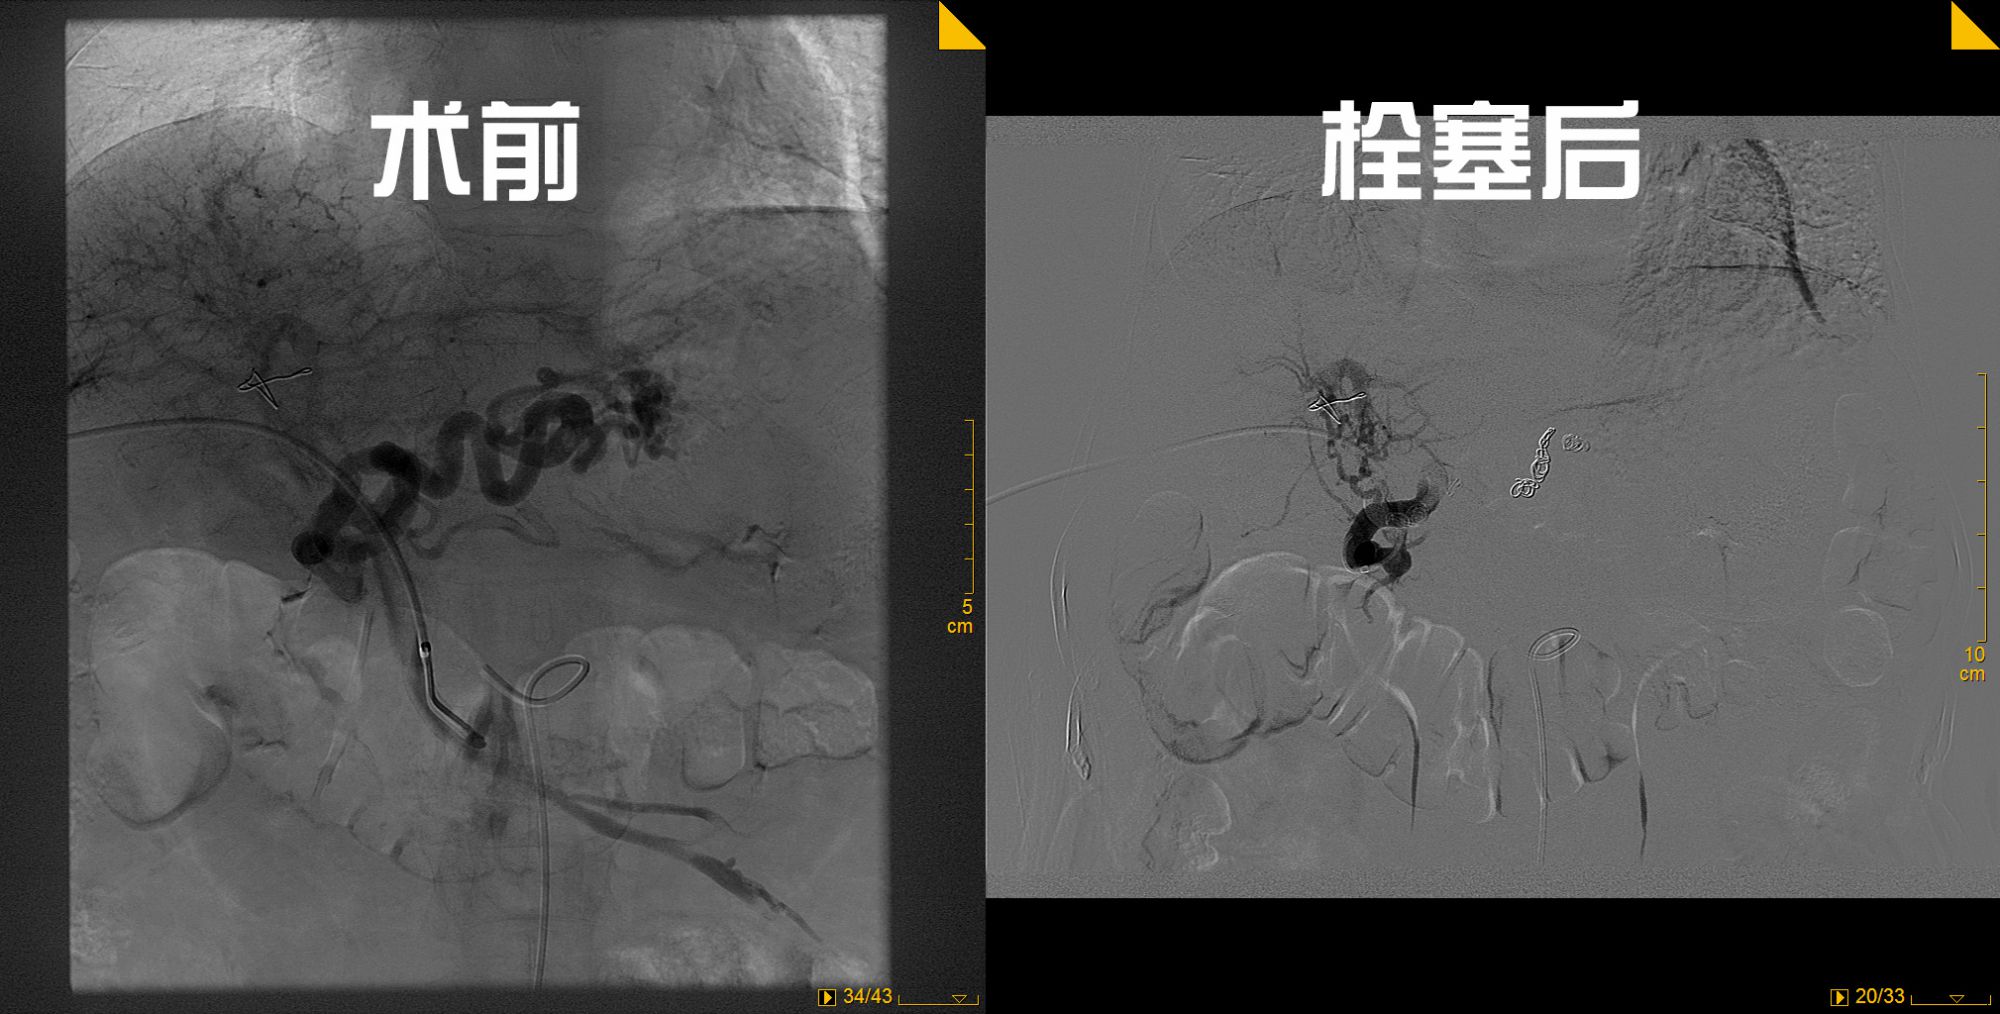

65岁的张女士,多年前曾因上消化道出血在外地医院诊断为肝硬化、门静脉高压、食管胃底静脉曲张,行脾切除+贲门周围血管离断术治疗。此次因呕血1500毫升来我院就诊,检查显示胃内大量积血、诊断为肝硬化、门静脉高压、急性上消化道出血。就诊期间又多次出现呕血,单纯药物治疗效果不佳,患者病情逐渐加重,呈失血性休克状态。介入血管外科会诊后,给予胃底食管曲张静脉栓塞术,手术顺利,术后患者未再呕血,病情稳定。

介入血管外科王立军主任介绍,门静脉高压是肝炎后肝硬化最常见的改变,由此引起的上消化道大出血非常常见。该类患者病情危急,部分患者药物治疗效果差,如出现反复出血,胃底食管曲张静脉栓塞术是首选治疗。